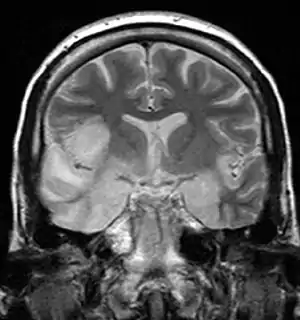

| Coronal T2-weighted MR image shows high signal in the temporal lobes including hippocampal formations and parahippogampal gyrae, insulae, and right inferior frontal gyrus. A brain biopsy was performed and the histology was consistent with encephalitis. PCR was repeated on the biopsy specimen and was positive for HSV | |